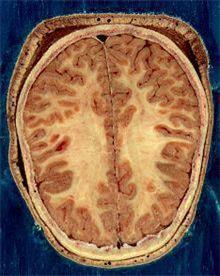

연구팀은 치료 전과 후 뇌 신경망의 연결 상태를 MRI 영상을 통해 비교하고 치료에 대한 반응도 평가했다.

우울증 환자는 치료를 시작한 지 불과 6주 만에 뇌 신경망의 신호 전달 상태가 급속히 호전된 것으로 나타났다.

우울증 치료가 환자 뇌의 인프라(기본조직)에 변화를 일으켜 신경 신호 전달 연결망이 크게 늘어난 것이라고 연구팀은 설명했다.

연구팀은 우울증 치료가 이처럼 빨리 뇌 신경망에 변화를 일으킨 데 놀랐다면서 이는 인간의 뇌가 전에 생각됐던 정도를 크게 뛰어넘는 유연성을 지니고 있음을 보여주는 것이라고 설명했다.